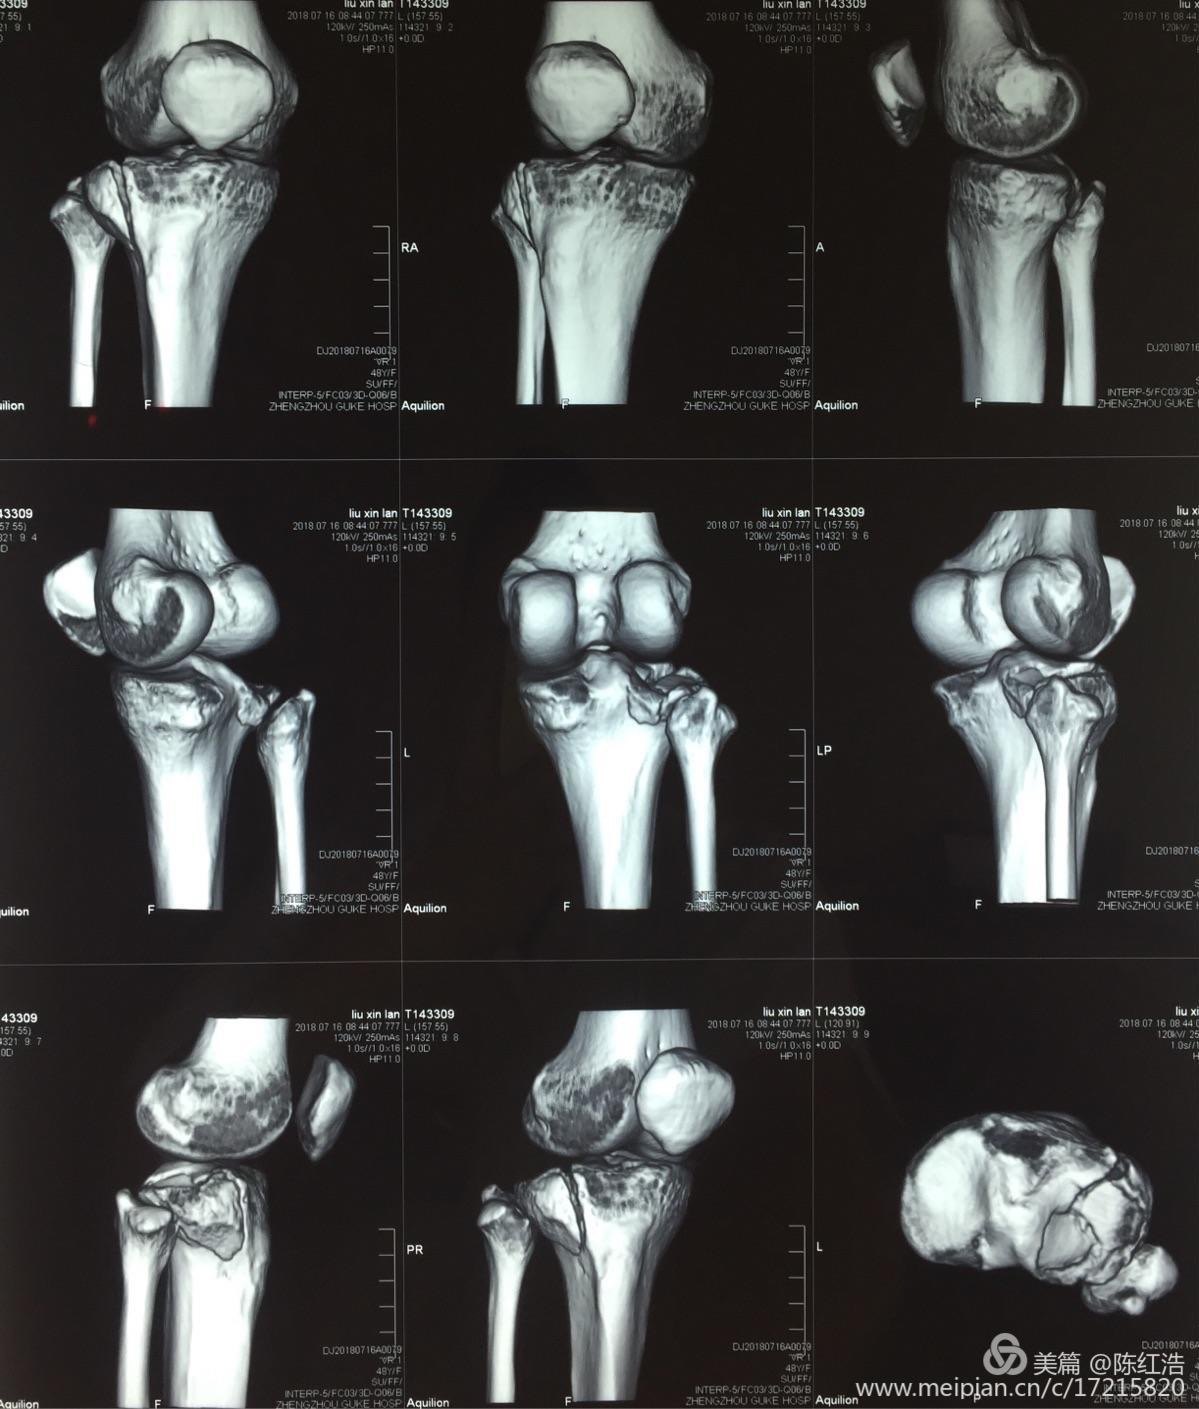

右胫骨平台粉碎性骨折 骨科与显微外科专业讨论版 爱爱医医学论坛

刘国辉 复杂胫骨平台骨折的手术治疗策略及病例分享 骨科在线

平台骨折不用愁 郑骨骨科解您忧 好大夫在线